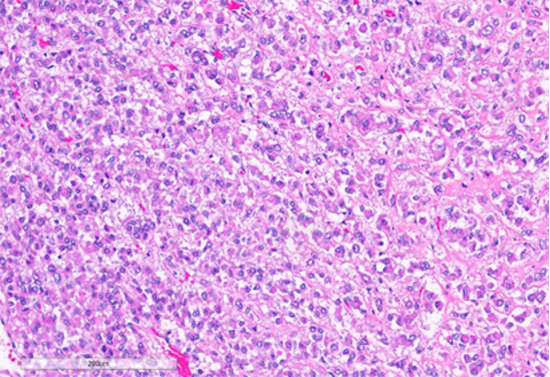

Figure 3: Tumor cells arranged in sheets and vague nests, with predominantly dense eosinophilic cytoplasm. (Hematoxylin and Eosin stained (10x)